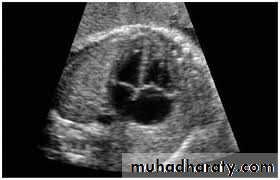

3-Echocardiography

The location and size of the atrial defect are readily appreciated by two-dimensional scanning . The shunt is confirmed by pulsed and color flow Doppler .